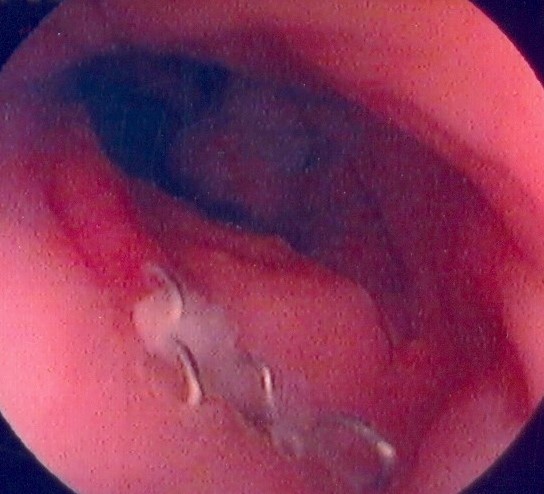

Endoscopic view of ileal pouch - anal anastomosis 3 years before the development of adenocarcinoma (Courtesy Dr. V. Penopoulos)